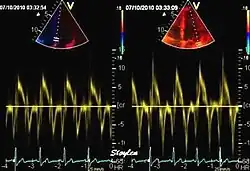

Like Doppler flow, tissue Doppler can be acquired both by spectral analysis (spectral density estimation) as pulsed Doppler[1] and by the autocorrelation technique as colour tissue Doppler[2] (duplex ultrasonography). While pulsed Doppler only acquires the velocity at one point at a time, colour Doppler can acquire simultaneous pixel velocity values across the whole imaging field. Pulsed Doppler on the other hand, is more robust against noise, as peak values are measured on top of the spectrum, and are unaffected of the presence of clutter (stationary reverberation noise).

This has become a major echocardiographic tool for assessment of both systolic and diastolic ventricular function. However, as this is a spectral technique, it is important to realise that measurement of peak values is dependent on the width of the spectrum, which again is a function of gain setting.